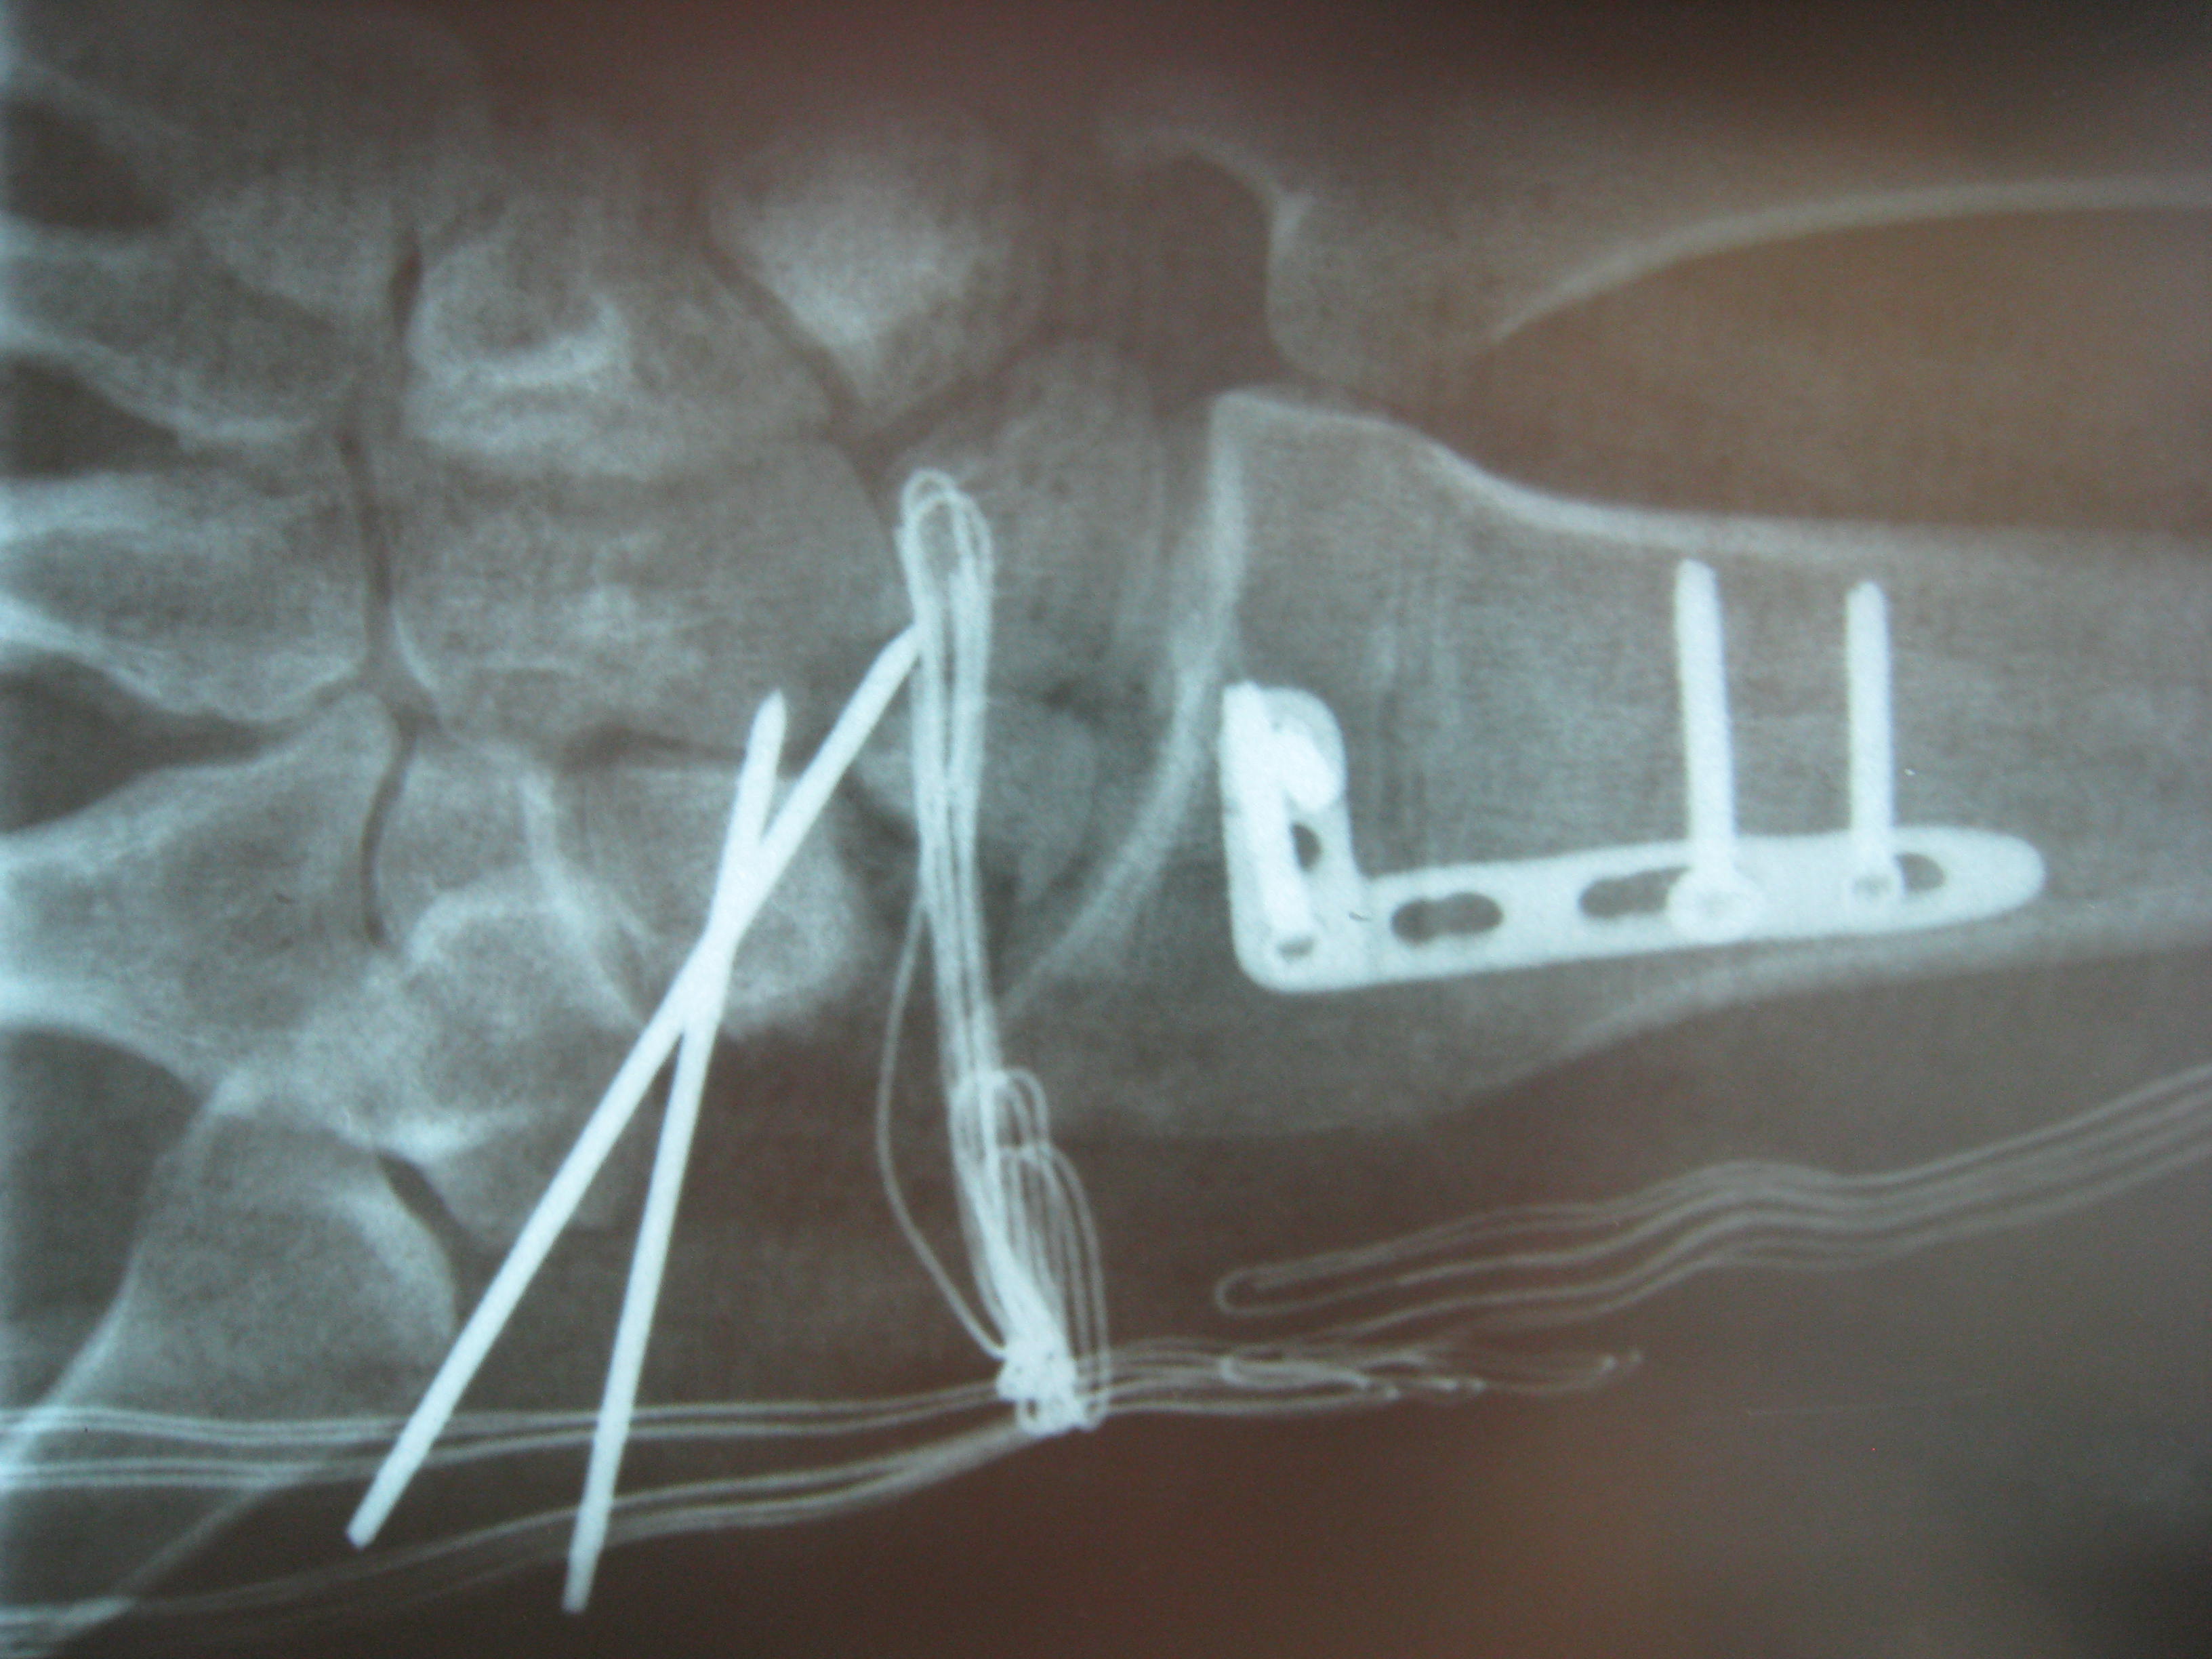

Περίπτωση 2: Μετεγχειρητικά 2

Η αντιμετώπιση της ψευδάρθρωσης του σκαφοειδούς είναι πάντοτε χειρουργική. Με ραχιαία ή παλαμιαία προσπέλαση αποκαθίσταται ο άξονας του σκαφοειδούς και σταθεροποιείται το σκαφοειδές με ειδική βίδα ή βελόνες, με παράλληλη τοποθέτηση οστικών μοσχευμάτων. Μπορεί επιπλέον να γίνει και οστεοτομία κλειστής σφήνας του περιφερικού άκρου της κερκίδος. Στις περιπτώσεις άσηπτης νέκρωσης το μόσχευμα πρέπει να είναι αγγειούμενο – για να προσδώσει αιμάτωση στο νεκρωμένο κεντρικό τμήμα – και λαμβάνεται με μικροχειρουργικές τεχνικές από το περιφερικό τμήμα της κερκίδος ή από άλλα τμήματα του σώματος